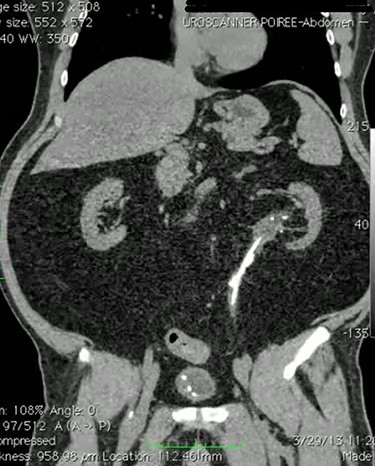

This is a case of 48-year-old man Hypertensive on medication who underwent bilateral percutaneous nephrolithotomy 10 years ago for bilateral renal stones. Patient was referred to our center as a case of left ureteric injury post Flexible URS for left middle and upper ureteric stones and was managed with left DJ stent. Abdominal CT scan showed stones in the left ureter with no leak (Fig. 1). Two months later, we decided to perform retrograde pyelography (RGP) and eventually ureteroscopy in order to clear his stones. RGP showed an invagination of mid-ureter about 4–5 cm (Fig. 2). A guidewire was passed under fluoroscopy guidance. Stones were removed and endoscopic exploration revealed ureteral intussusception (Fig. 3). DJ stent was inserted, and 6 weeks later, we performed a nuclear scan (MAG3) that showed obscure drainage from the left kidney. Therefore, ureteral reconstruction with ileal interposition was our option to overcome this complication. Patient underwent the surgery uneventfully and was followed up after surgery for 6 months and was pain free with no significant hydronephrosis or change in renal function.

CT scan of abdomen showing left JJ stent in place with multiple upper ureteric stones with obvious leak.